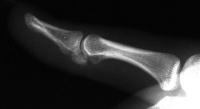

Case 1. 14 year old boy with radial prominence and ulnar deviation of the middle finger proximal interphalangeal joint. Painless, no history of trauma.

Radiographs showing well circumscribed calcification at the  proximal phalanx collateral ligament origin, 10 degrees of lateral angulation.